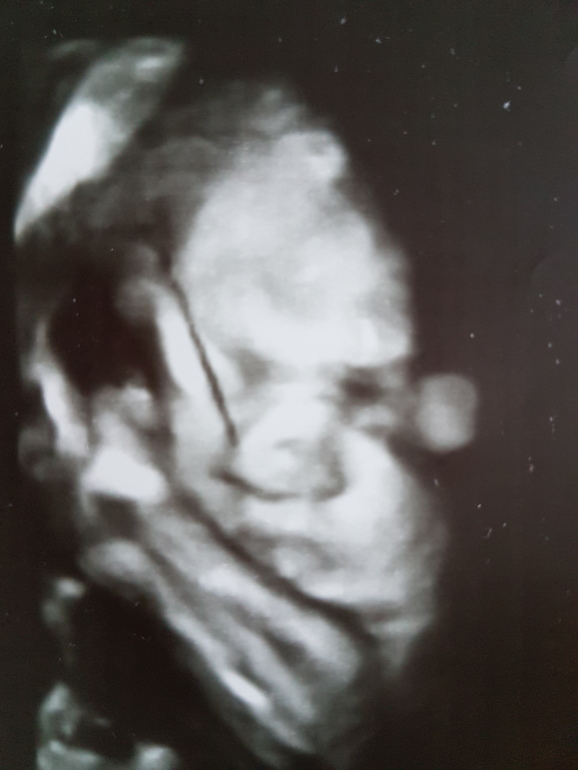

Главное что нет белка в моче!😊 Ож 91 (+3), вдм 32 ( +2), вес 59, 4 ( +0,9), доча в головном чсс 145. Опять сдавать кучу крови, записалась на ктг. Следующий прием 10 марта. И наши фотки в соответствии с замерами.